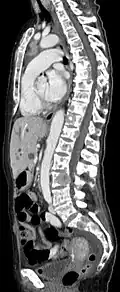

- Comparaison scanner/IRM pour des métastases ostéolytique d'un cancer du sein dans la colonne vertébrale

IRM natif avec pondération T1.

IRM sagittal natif avec pondération T1. On voit clairement l’extension jusqu'aux lames vertébrales.